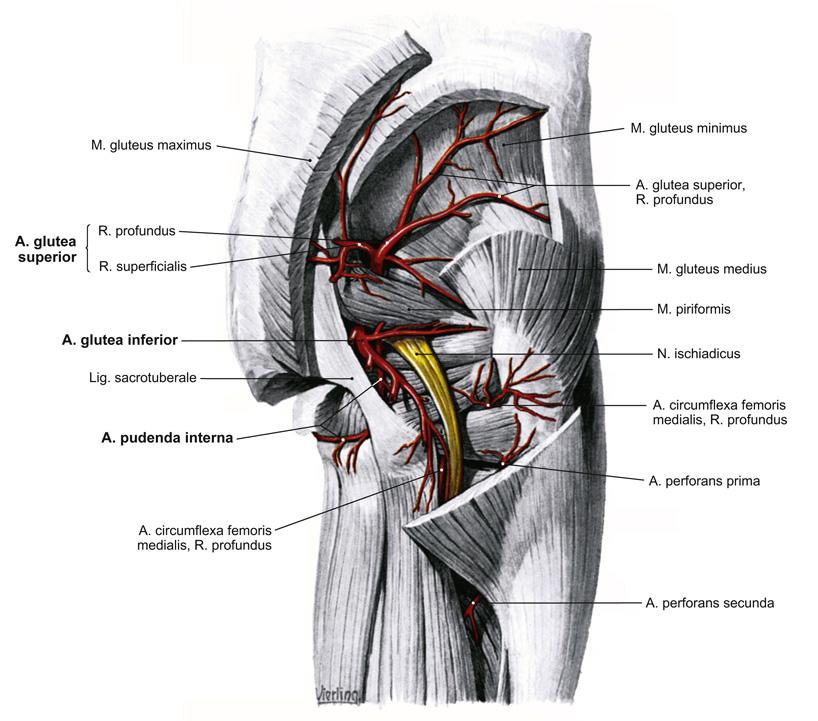

Fig 3.27: a. iliaca interna - dorsale hoofdstam

A doorsnede

os pubis sacrum -

a iliolumbalis

a sacralis lateralis -

a glutea superior

r superficialis r profundus

B vooraanzicht

C zijaanzicht

os coxae > os ilium lig sacrotuberale -

lig sacrospinale